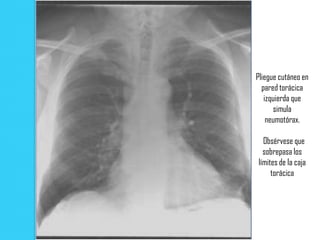

Radiografía PA: pliegues cutáneos que simulan un neumotórax. Línea pleural aparente (flechas) no se extiende

mas allá del margen torácico. Hay aumento gradual de la opacidad pulmonar desde la parte medial hacia la zona

lateral. La opacidad es máxima en el borde interno de la línea y luego disminuye en forma abrupta.

Pliegue cutáneo en

pared torácica

izquierda que

simula

neumotórax.

Obsérvese que

sobrepasa los

límites de la caja

torácica